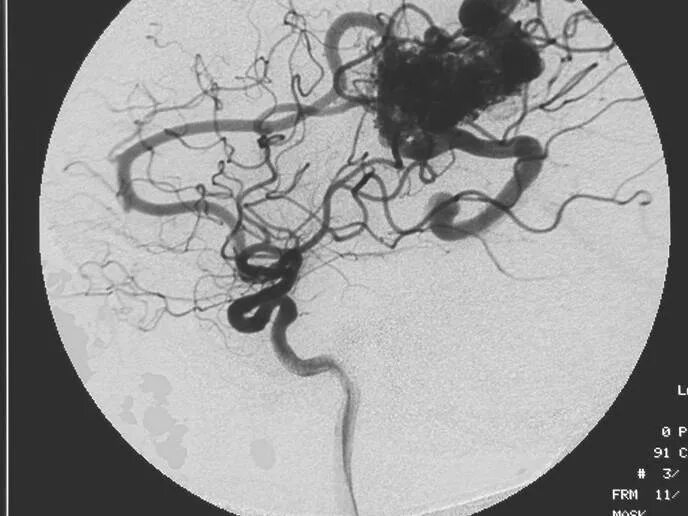

Мальформация сосудов